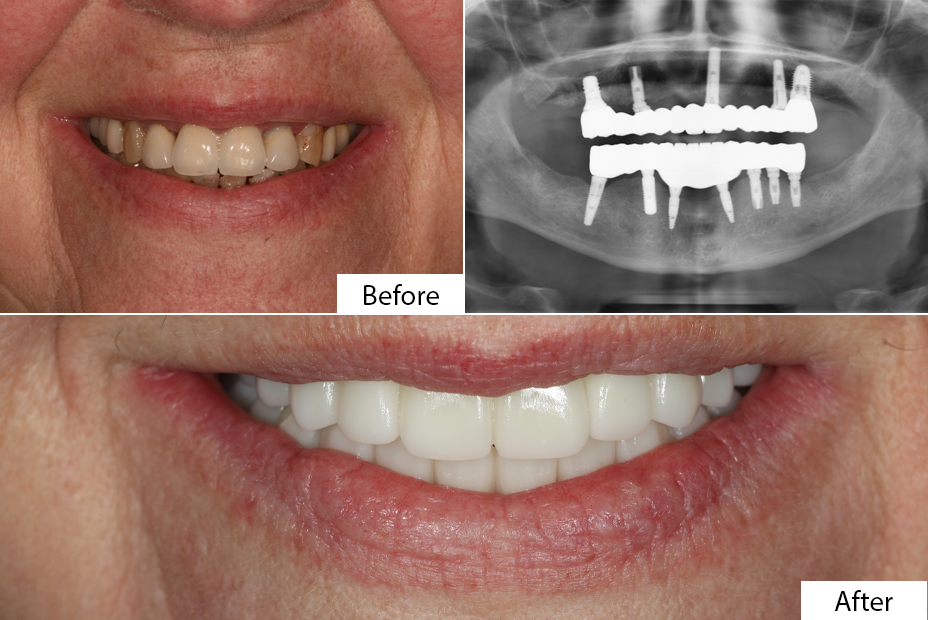

A dental implant is an artificial replacement for a missing tooth root. It is typically made of titanium, which integrates with the jawbone and provides a stable foundation for attaching a crown, bridge, or denture. Unlike removable options, implants function almost like natural teeth and preserve surrounding bone.

Patients often compare implants with bridges and dentures. While dentures may seem affordable, they can slip, cause discomfort, and require frequent replacement. Bridges are fixed but put pressure on supporting teeth. Implants, on the other hand, are permanent, provide a natural look, and restore full bite strength.

The process begins with a detailed examination, X-rays, and sometimes 3D scans. The dentist checks bone density, gum health, and overall suitability for implants. - Surgical Phase

During surgery, a titanium post is placed into the jawbone. This serves as the artificial root. Depending on the case, patients may receive an immediate implant or require healing time before restoration. - Healing and Integration

Over the next few months, the implant fuses with the bone in a process called osseointegration. This step is crucial for stability and long-term results. - Restorative Phase

Once healed, a crown, bridge, or denture is attached to the implant. Patients may use a temporary prosthesis during the healing phase until the final restoration is fitted.